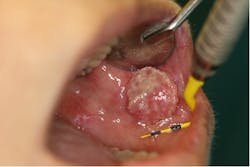

Squamous cell carcinoma

In the US, oral cavity squamous cell carcinoma (OC-SCC; figure 9) is the most common malignancy of the head and neck, apart from nonmelanoma skin cancer. Risk factors include all forms of tobacco use, alcohol abuse, and the human papillomavirus (HPV).11 OC-SCC is preceded by leukoplakia (white), erythroplakia (red), or erythroleukoplakia mixed/speckled-type lesions that present on the tongue, floor of the mouth, buccal mucosa, labial mucosa, retromolar trigone, and soft palate.11 The value of the clinical oral exam cannot be underestimated. Due to the frequency of the hygiene schedule, dental hygienists are a first line of defense in knowing their patients’ oral health and, as such, can play a vital role in early intervention and saving lives.